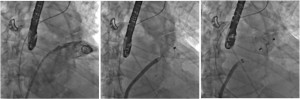

ICPS(写真1)という施設はパリ郊外のMassyという所にあるcardiology、特にinterventionがメインの病院で、年間1万件ほどのCAGおよび2000件前後のPCIを施行しているhigh volume centerです。またcoronary interventionだけでなく、TAVI、MitraClip、LAA閉鎖術(写真2)といったstructural heart disease (SHD)に対するinterventionもさかんに行われております。特にaortic stenosis (AS) に対するTAVIに関しては、週5〜6件、年間200件以上の症例を施行しており、Edwards SapienXTやCoreValveといった第1世代でバイスだけでなく、Edwards Sapien3(写真3)やLotus valveといった第2世代デバイスも積極的に使用している施設です。

Arai1-2

写真2